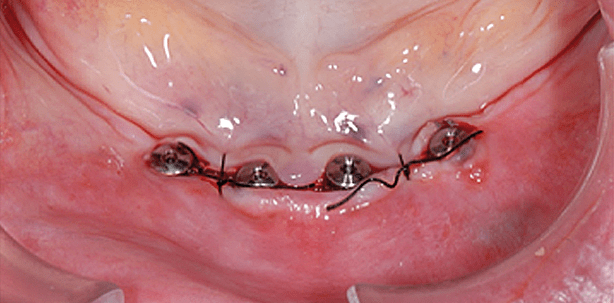

Abb. 1 und 2: Komplikationslose Implantation von vier interforaminären Implantaten bei einer 74-jährigen Patientin unter langjähriger Steroid- und Betablockermedikation mit fortgeschrittener mandibulärer Atrophie. – Abb. 3: Röntgenbild.